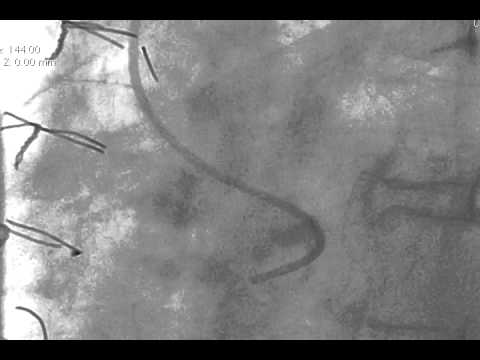

Video 7.5

Video 7.5: Engaging the RCA with the MP catheter